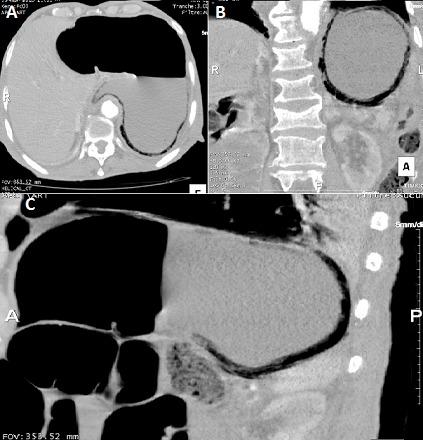

[A rare and fulminant form of gastritis: emphysematous gastritis].

https://cdn.ncbi.nlm.nih.gov/pmc/blobs/05e6/4725653/230014efbfda/PAMJ-22-58-g001.jpg